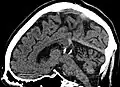

Pinealiszyste

(Sagittalschnitt in MRT, magnetresonanz-tomographisch erstelltes Kernspinresonanzbild) -